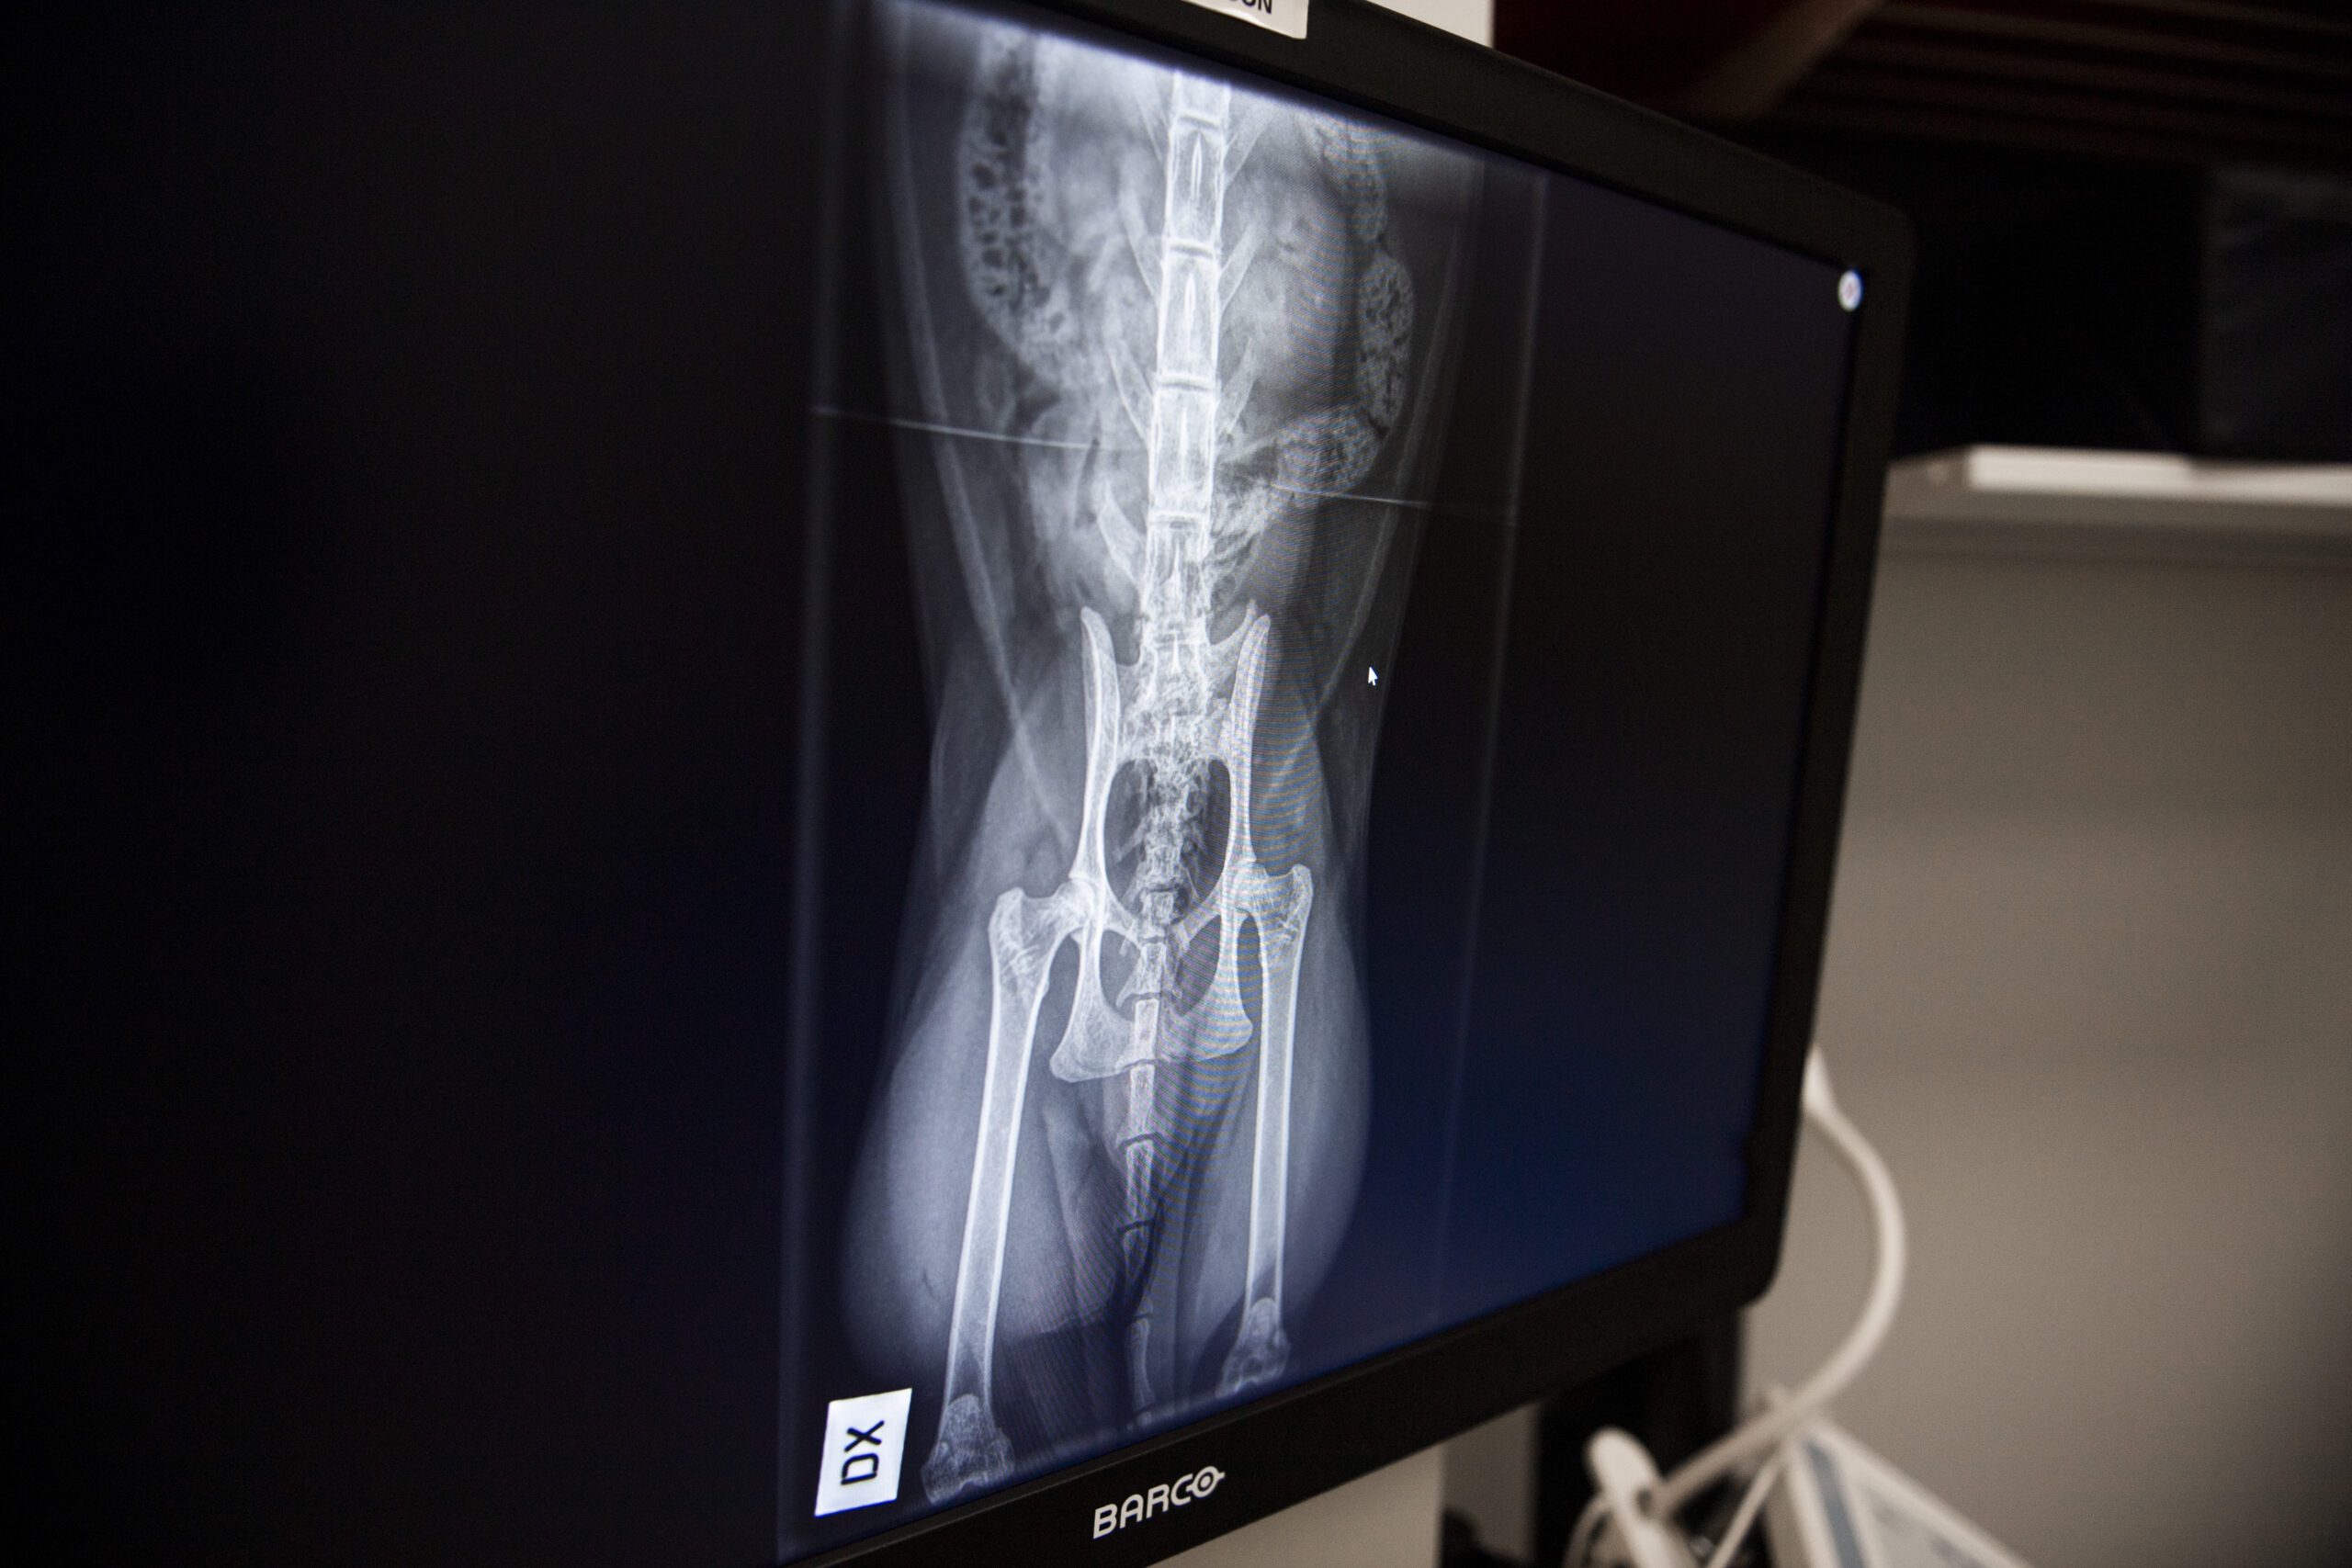

Otamme myös PEVISA-kuvia koirista

• Lonkkanivel, kyynärnivel, olkanivel, selkäranka

• Käytössämme on digitaalinen röntgenlaitteisto, joka takaa hyvän kuvanlaadun ja siten optimaalisen diagnostisen arvon. Pystymme myös tarvittaessa lähettämään kuvia radiologille tai ortopedille jatkolausuttavaksi sähköisessä muodossa.

• Lisäksi röntgenkuvausta käytetään koirien ja kissojen virallisten terveystarkastusten yhteydessä (mm. PEVISA).